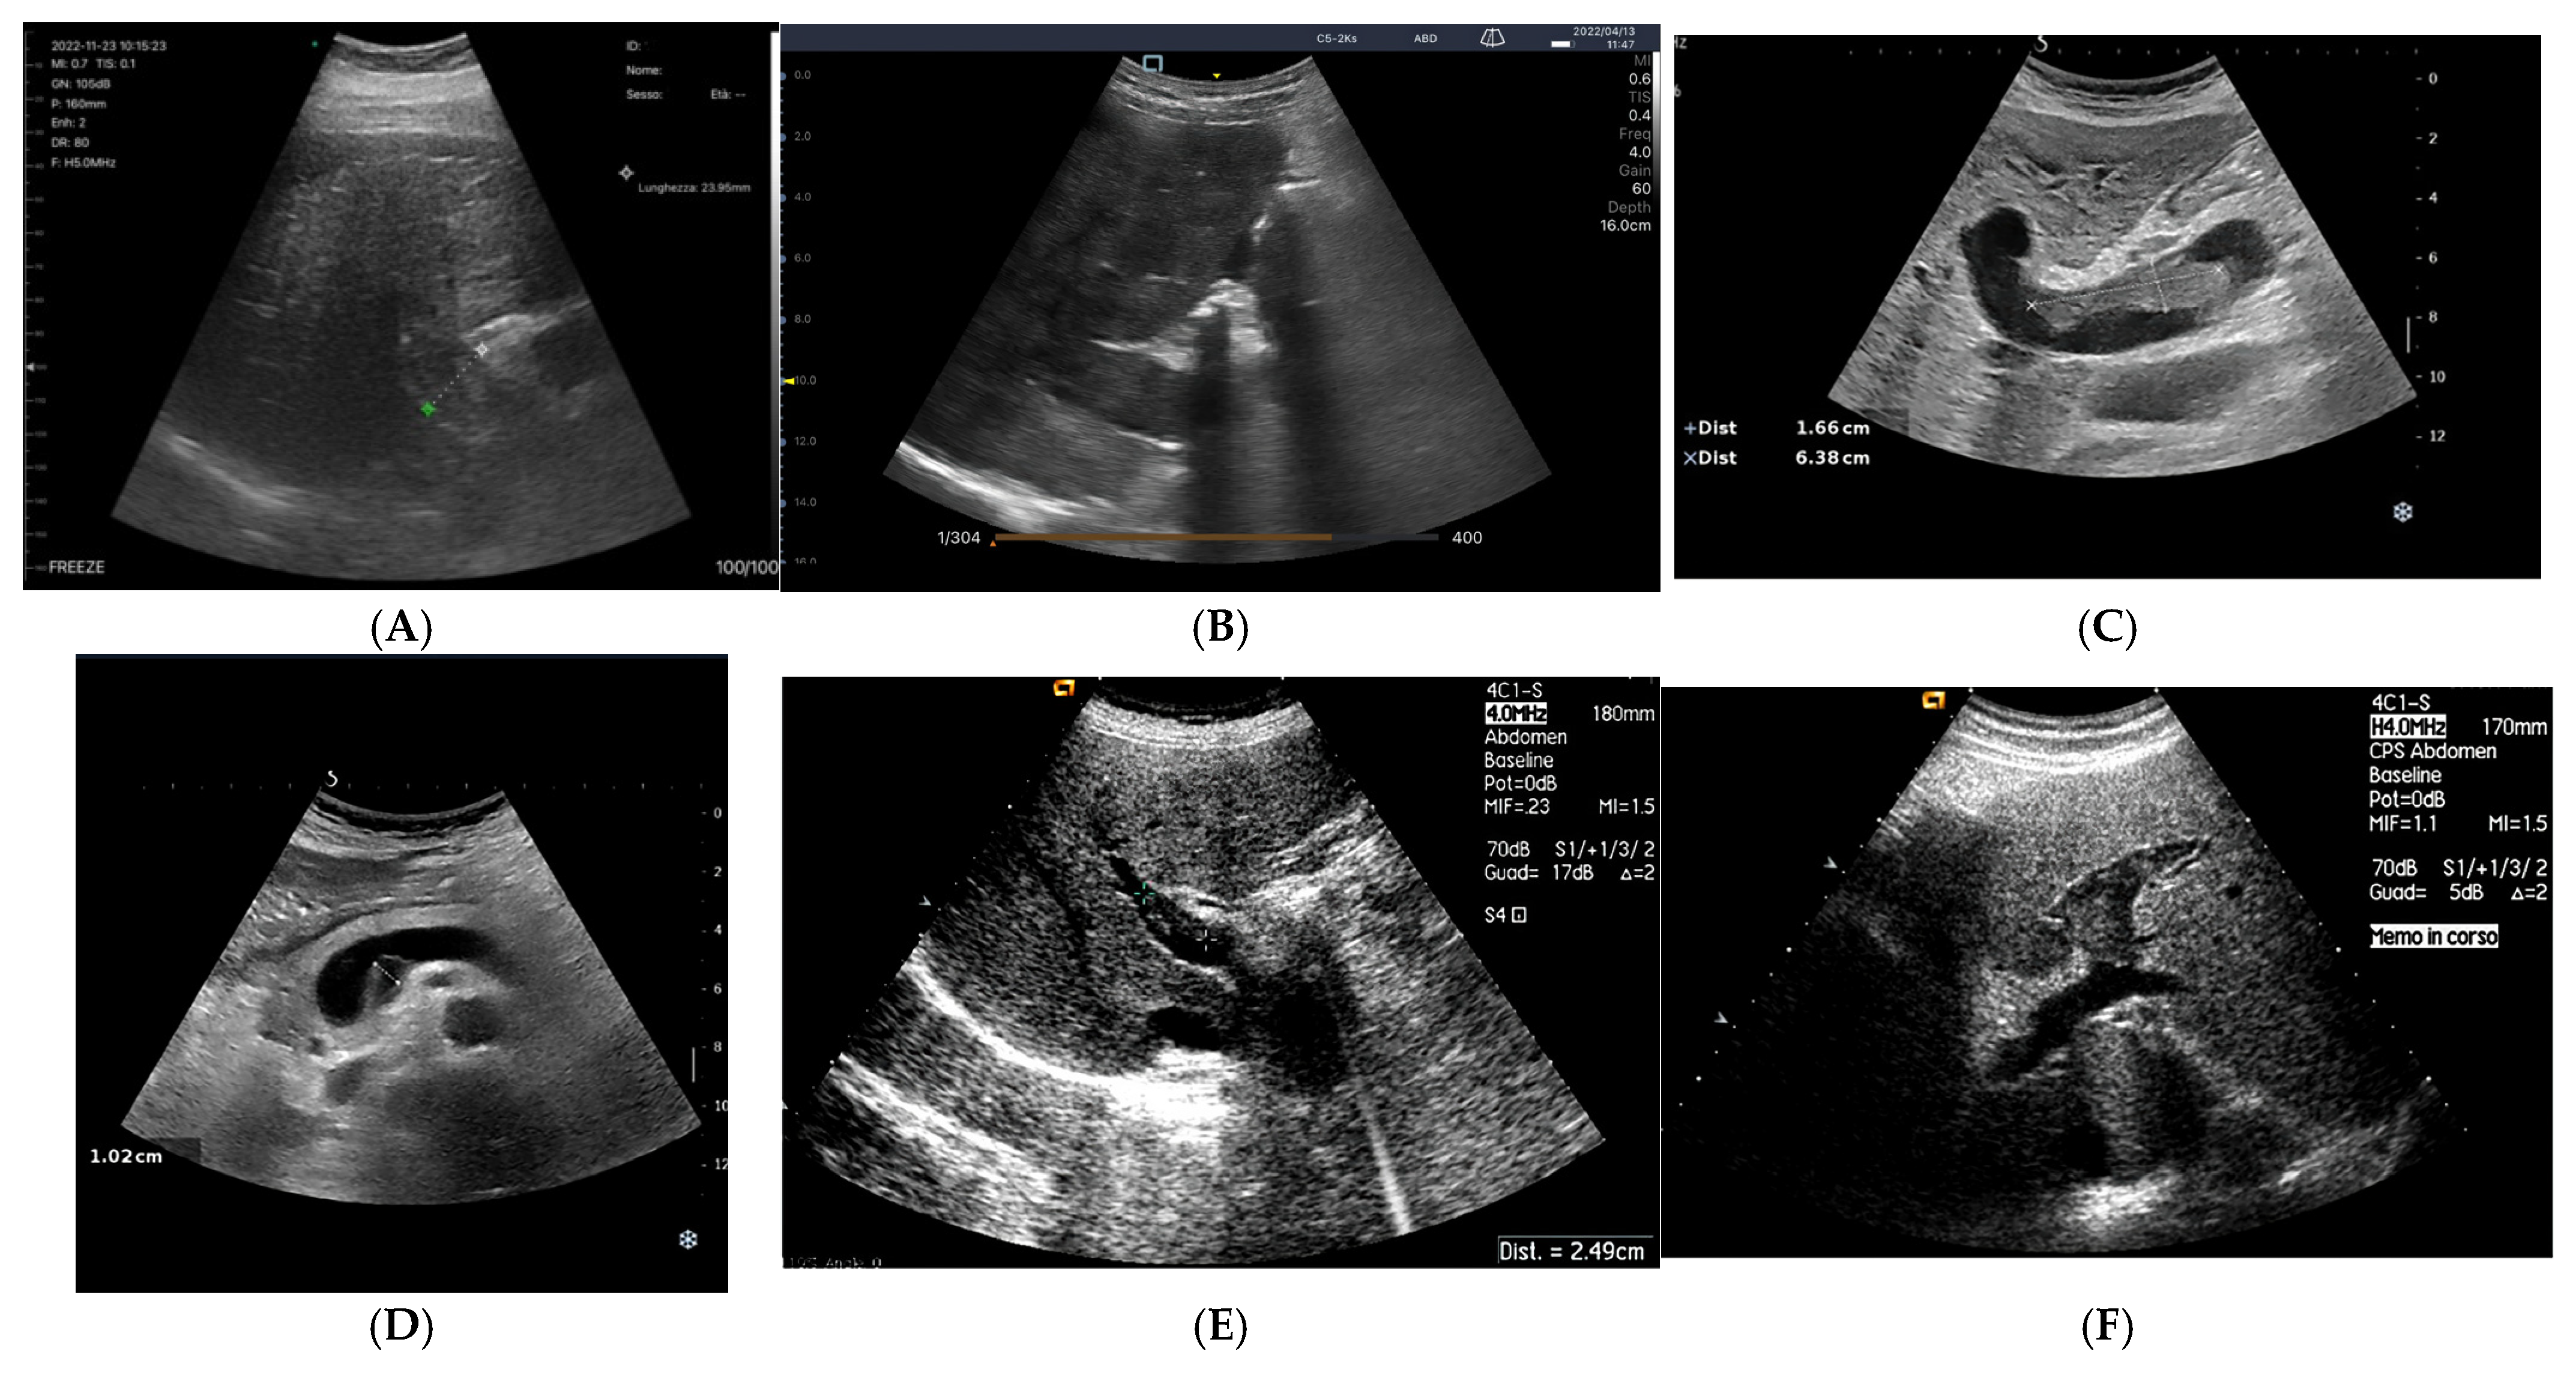

3.1.1. B-Mode

Bowel-Wall Thickening

Venous Congestion

3.1.4. Arterial Hypovascularization

B-Mode Renal Ultrasound and Renal Artery

Color-Doppler: Renal Resistive Index (RRI)